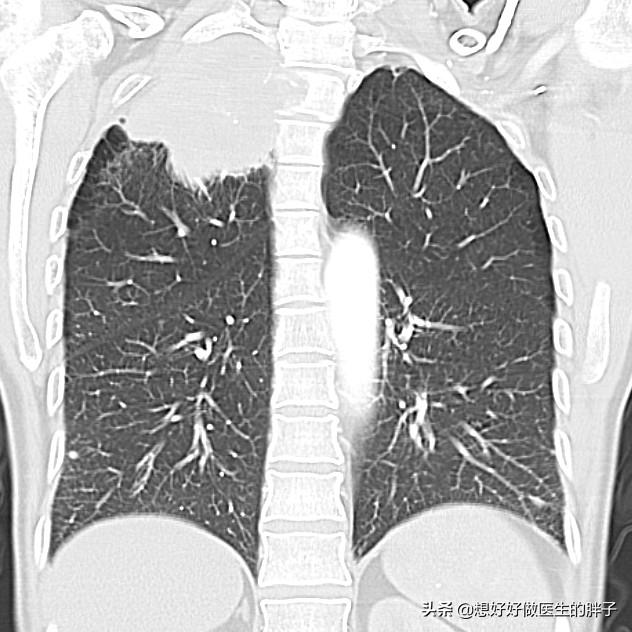

●肺疾患..肺の病気が肩こりや背部痛を発症させることは比較的まれであるが、肺がんの一種として、以下のようなものがある。肺尖癌しかし、腫瘍が成長するにつれて、胸膜に徐々に浸潤し、肩背部の痛みを誘発することがある。

これが疑われる場合、次のことを行うことが重要である。肺のCTスキャンプレースホルダーがあるかどうかを明らかにする。